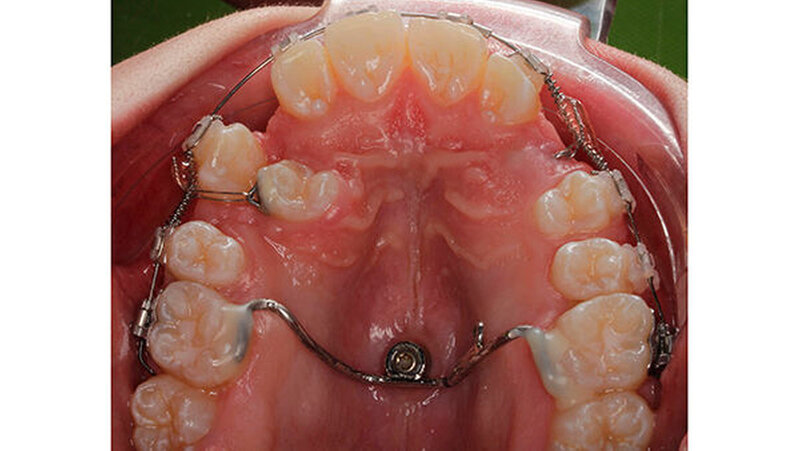

Im Laufe der Behandlung wurde Zahn 13 mesialisiert, um die Transposition mit Zahn 14 aufzulösen. Nachdem die Kronen der verlagerten Zähne soweit durchgebrochen waren, dass ein Bracket geklebt werden konnte, wurden sie mithilfe der Overlaybogentechnik in den Zahnbogen eingestellt. Die Wurzelaufrichtung des Zahn 14 fand mit einer Aufrichtefeder statt. Die restlichen Zähne wurden dabei mit einem 19 x 25 Stahlbogen stabilisiert.

Nach dreijähriger kieferorthopädischer Behandlung konnte die Patientin entbändert werden. Eine Stabilisierungsphase mit herausnehmbaren Essixschienen folgte. Nach Ende der aktiven Behandlungszeit waren die Therapieziele weitgehend erfolgreich umgesetzt worden.